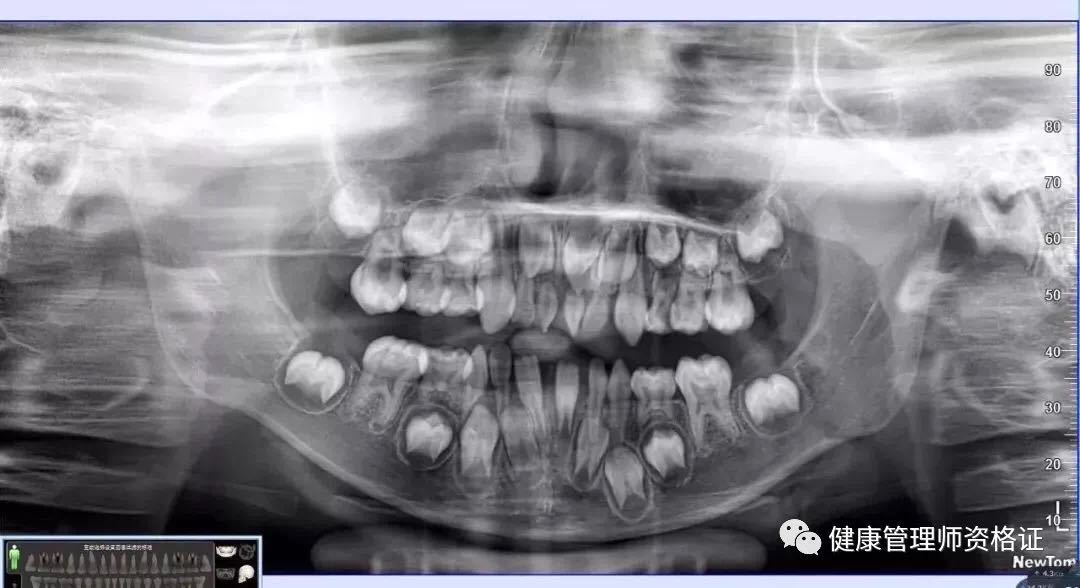

(1) 全景曲斷片

以檢查全口牙齒為目的,全景曲斷片可以觀察到全口牙的形態、位置、頜骨等情況,比如乳牙下方是否有恒牙牙胚在發育、牙頜的畸形程度等等。